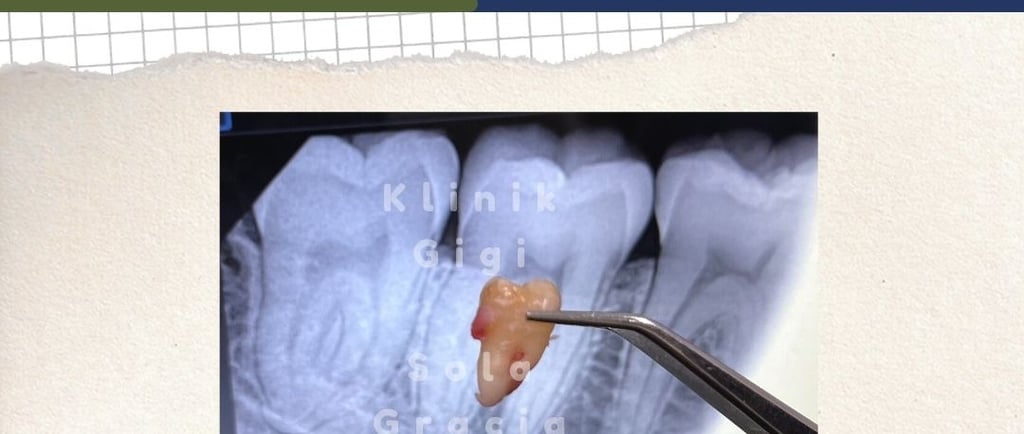

Operasi Gigi Bungsu